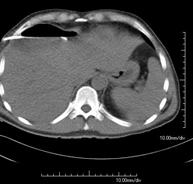

Prueba diagnóstica que consiste en obtener imágenes del abdomen de alta definición anatómica (hígado, vesícula biliar, vía biliar, páncreas, bazo, estómago, intestinos, riñones, estructuras vasculares, vejiga, útero y ovarios, etc.) mediante el empleo de un equipo de TC (Tomografía Computarizada). Dichas imágenes se estudian posteriormente en una estación de trabajo que permite reconstrucciones bidimensionales en diferentes planos del espacio, y también reconstrucciones 3D (volumétricas). La mayoría de estudios requieren el empleo de contraste yodado para mejorar la definición de las imágenes. - TC Pelvis

Prueba diagnóstica que consiste en obtener imágenes bi y tridimensionales del abdomen y de la pelvis de alta definición anatómica (estructuras óseas, estructuras vasculares, hígado, páncreas, vesícula biliar, riñones, glándulas suprarrenales, bazo, intestino delgado y grueso, vejiga, útero y ovarios, próstata y vesículas seminales, uréteres, etc.) mediante el empleo de un equipo de TC (Tomografía Computarizada). La mayoría de estudios requieren el empleo de contraste yodado. - TC Hígado

Prova diagnòstica que consisteix en obtenir imatges de l'abdomen d'alta definició anatòmica (fetge, vesícula biliar, via biliar, pàncrees, melsa, estómac, intestins, ronyons, estructures vasculars, bufeta, úter i ovaris, etc.) mitjançant l'ús d'un equip de TC (Tomografia Computeritzada). Aquestes imatges s'estudien posteriorment en una estació de treball que permet reconstruccions bidimensional en diferents plans de l'espai, i també reconstruccions tridimensionals (3D: volumètriques). La majoria d'estudis requereixen l'ús de contrast iodat per millorar la definició de les imatges. - TC d'estudi rotacional EEII